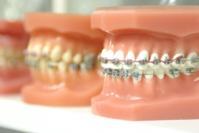

What is an Orthodontic?

Orthodontic is not just about straighter teeth. It also can improve your facial balance!

Several issues below that we can work with you to correct:

Overcrowded teeth occur when there is simply a lack of room within your jaw for all of your teeth to fit normally. When left untreated, overly crowded teeth can cause an increased chance of gum disease as your teeth are harder to clean and can prevent the normal function of teeth. Overcrowded teeth Widely spaced teeth occur when you have extra space within your jaw. This could be due to small sized teeth, abnormal growth of jaw bones, genetics, missing teeth and/or tongue protrusion. When teeth are missing, this can also be caused by the other teeth shifting due to extra space. Spacing issues can cause some perio-dontal diseases including gingivitis and periodontitis, that, left untreated, can lead to tooth loss. Widely spaced teeth